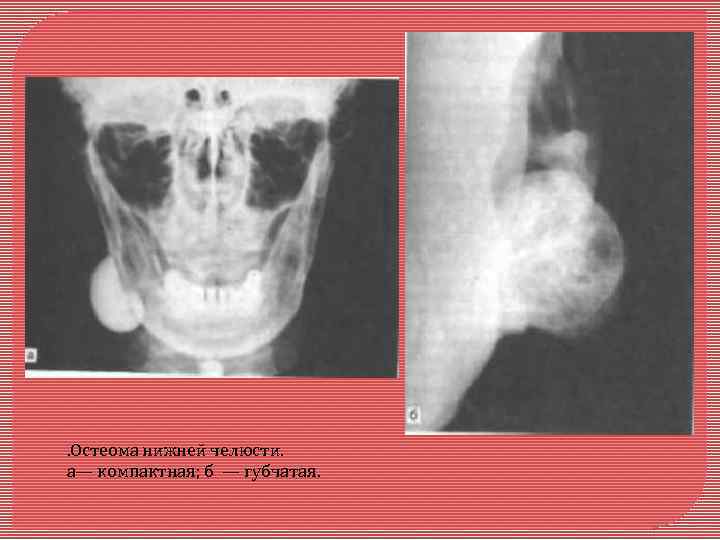

Остеома - доброкачественная костная опухоль. Чаще возникает у женщин молодого и среднего возраста. Характеризуется медленным ростом. Локализация: челюстные и другие кости черепа. Выделяют центральную и периферическую остеому. Центральная остеома развивается из эндооста, периферическая - из периоста. Периферическая остеома макроскопически округлой или неправильной формы, консистенции костной плотности, соединена с челюстью широким или узким основанием. Размер опухоли чаще всего от 1 до 2 см. При больших размерах может вызывать деформацию лица. Центральная остеома макроскопически располагается в глубине челюстной кости, небольших размеров до 1, 5 см, кортикальный слой не разрушается. Микроскопически остеомы делят на губчатые и компактные

. Остеома нижней челюсти. а— компактная; б — губчатая.